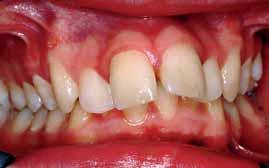

The patient had moderate Class II skeletal pattern with average Frankfort-mandibular planes angle and lower anterior face height. There was no facial asymmetry and the lips were incompetent with the lower lip trapped at rest behind the upper central incisors (Figure 1).

The oral hygiene was fair but needed improvement prior to orthodontic treatment. All teeth from the left permanent second molar to the right have erupted in both the upper and lower arches. The patient had carious lesions in both upper first molars, upper left second molar and lower left first molar. The maxillary arch was spaced with a midline diastema. Furthermore, there was mild lower labial segment crowding (4mm). The incisor relationship was Class II division 1, the overjet was 12 mm whereas the overbite was increased and complete to the palate

and causing trauma to the palatal mucosa. The centrelines were coincident and the buccal segment relationship was 1/2 unit Class II on both sides (Figure 2).